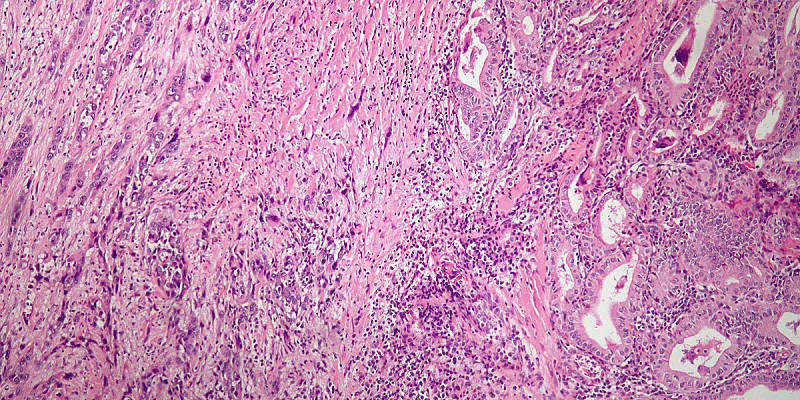

Carcinoma follicolare della tiroide, quali sono i fattori di rischio per mortalità

Anche se la prognosi del carcinoma follicolare rimane buona, e alcuni studi hanno documentato una prognosi simile a quella del PTC quando i pazienti erano “matched

Anaplastic_thyroid_carcinoma_low_mag